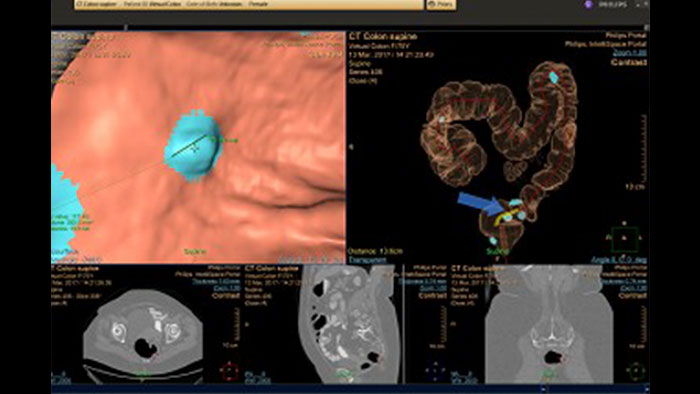

Reducing reading times in virtual colonoscopy

Enables 3D visualization of colon scans. The application automatically segments the air-filled colon and displays a calculated navigation path. The Perspective Filet view provides a synchronized display of the full colon surface wall with a single unidirectional view, reducing the need to review in both directions.